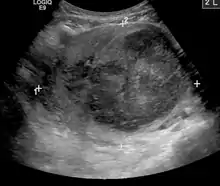

| A very large (9cm) fibroid of the uterus which is causing pelvic congestion syndrome as seen on X-ray computed tomography | |